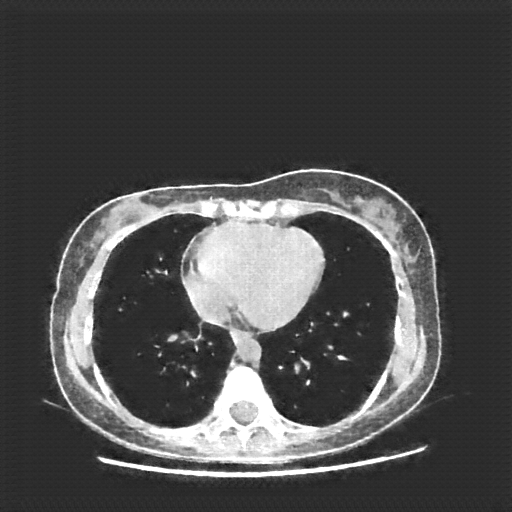

Generated VENOUS CT scan (A→B translation)

Full window (WL 1023.5, WW 4095 β†’ Low βˆ’1024, High +3071)

Lung window (WL -600, WW 1500 β†’ Low βˆ’1350, High +150)

Mediastinum window (WL 40, WW 400 β†’ Low βˆ’160, High +240)